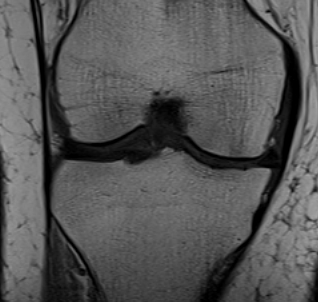

MRI

Classification

Grade I: intact ligament with periligamentous oedema

Grade II: partial tearing with surrounding oedema

Grade III: complete ligament tear

Sites

Femoral avulsion

Midsubstance

Tibial side: wave sign, ensure that the MCL is no flipped above pes anserinus as will not heal (analogous to Stener lesion)

Acute femoral avulsion

Midsubstance MCL tears

Wave sign indicative of tibial avulsion, with ligament retracted above pes anserinus / hamstring tendons

In the chronic setting see thickening of the MCL